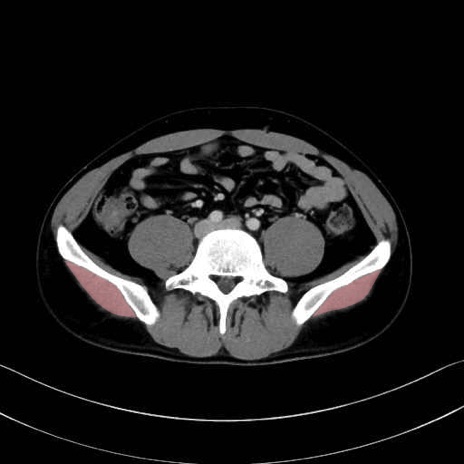

中殿筋 (Gluteus medius)